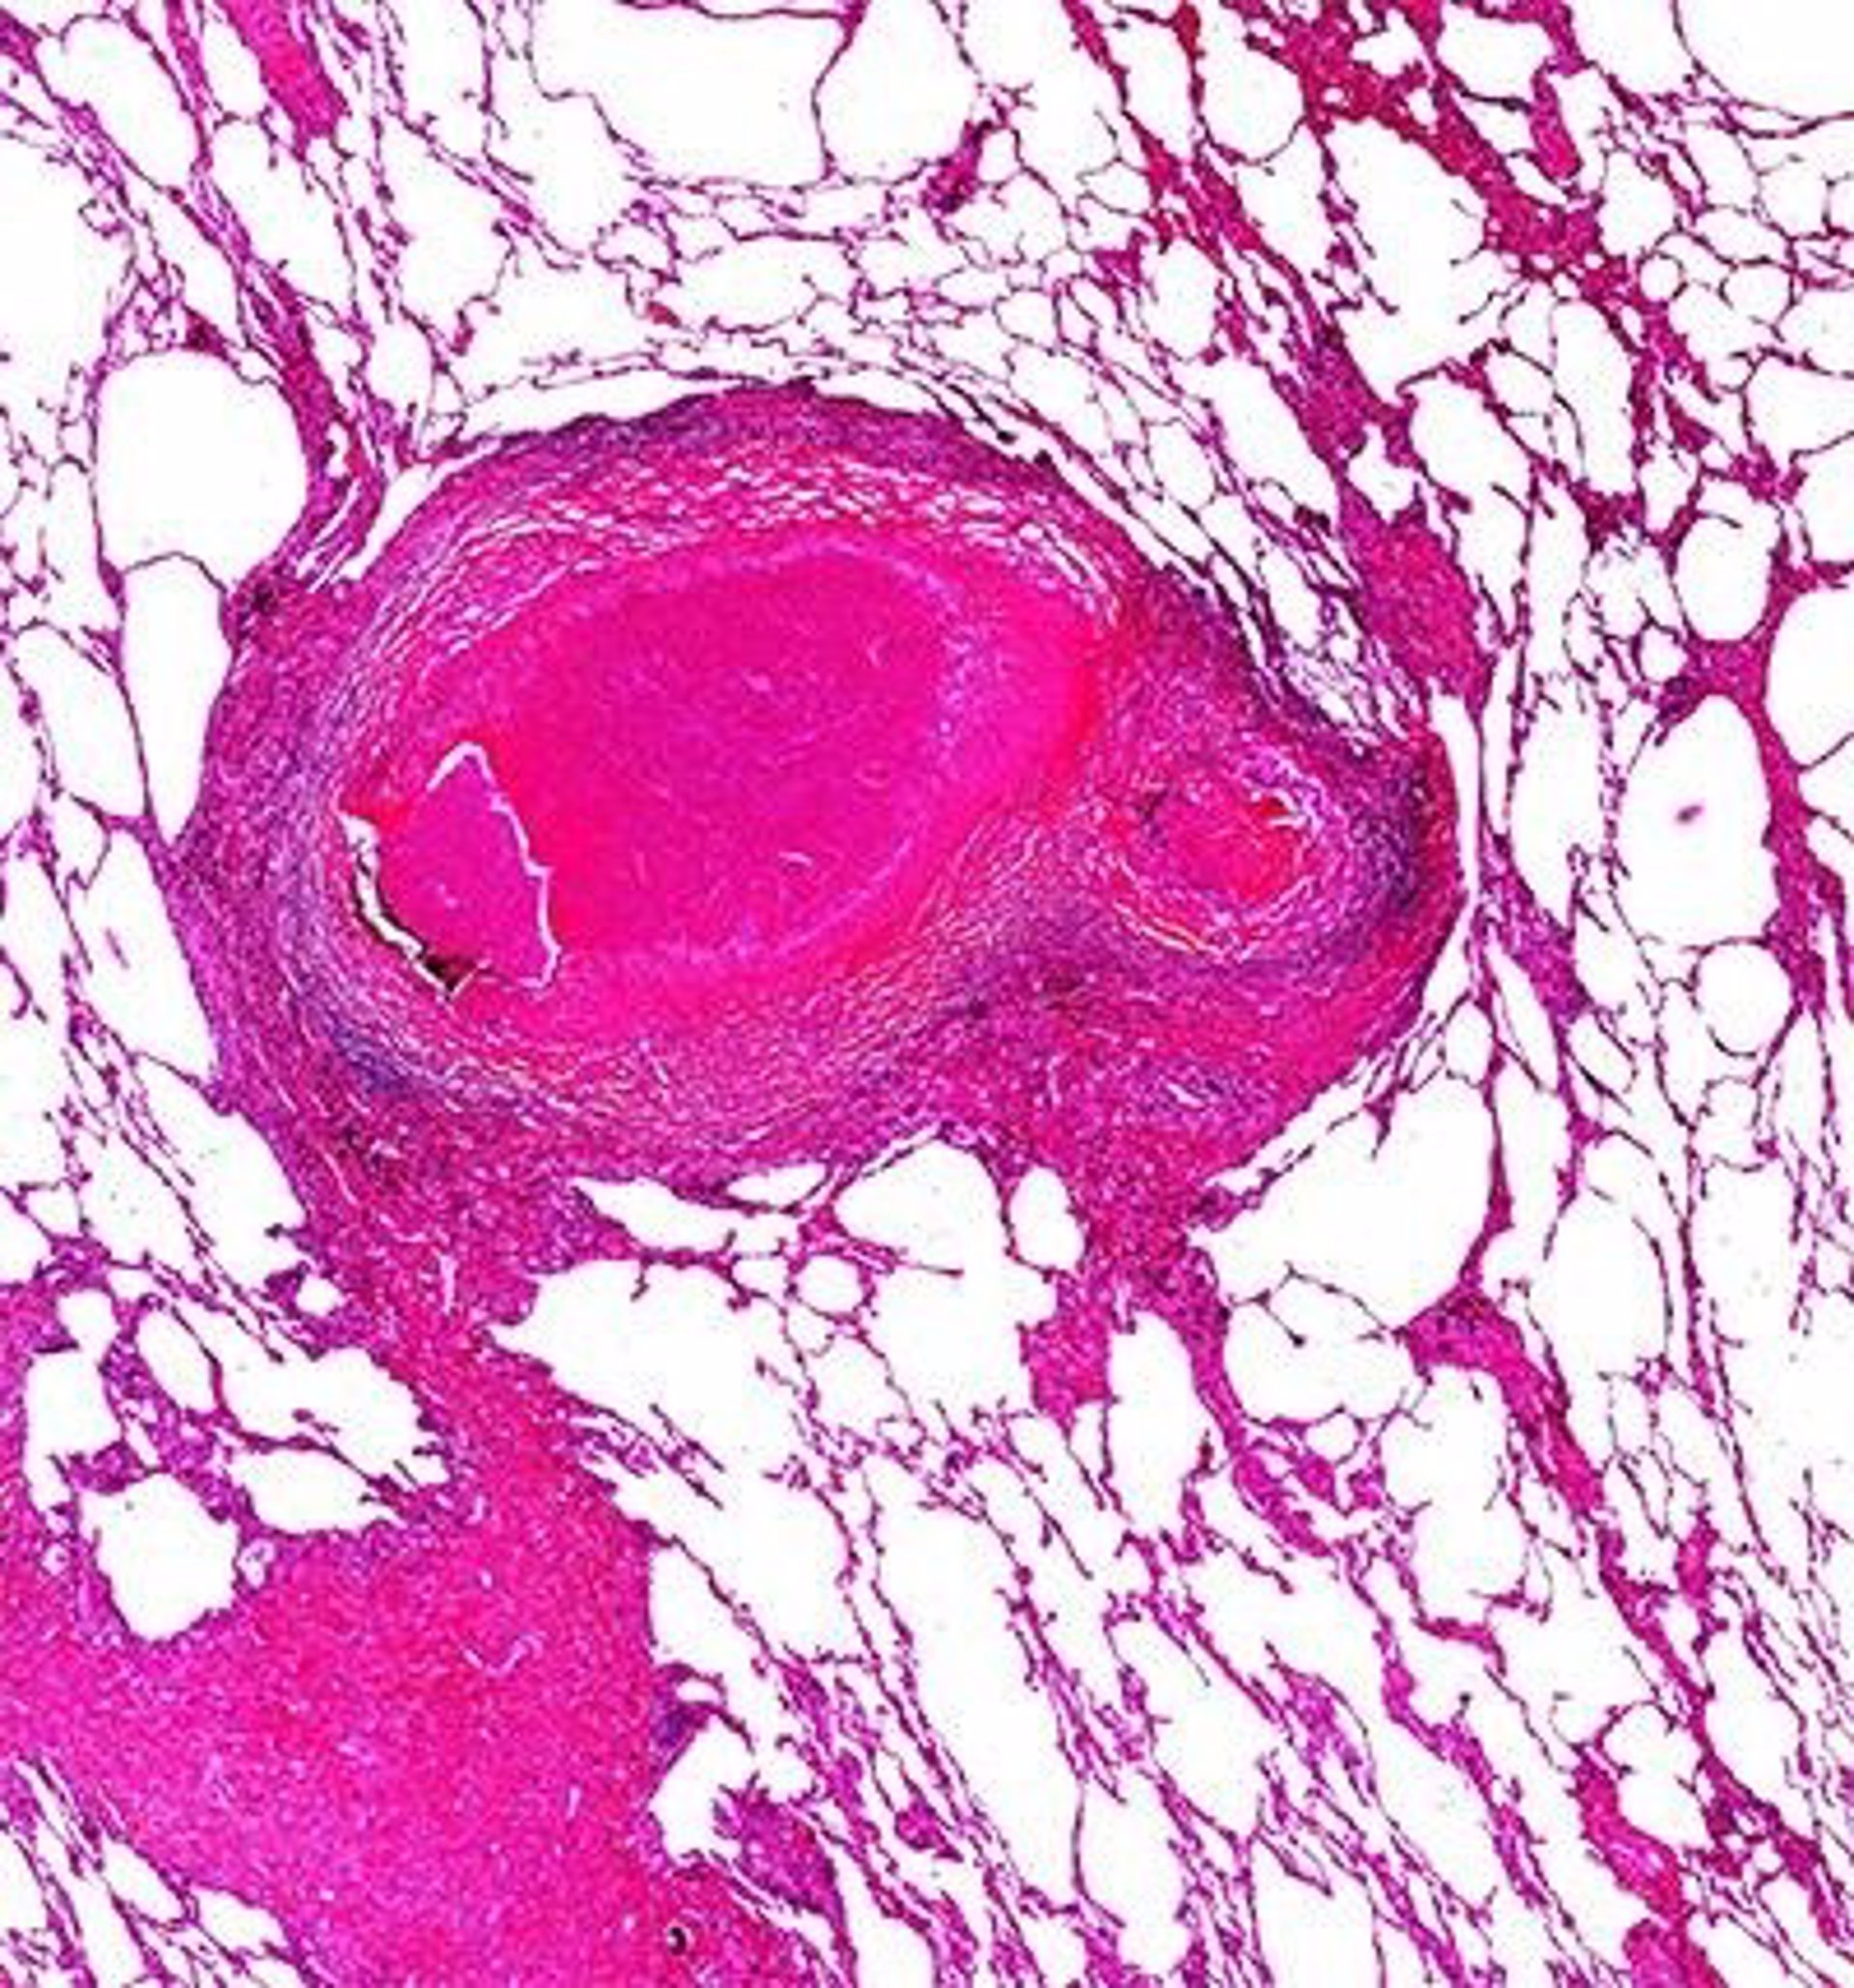

VALÈNCIA. (EP) Un 88,7% del total de pacientes con tuberculosis en la Comunitat Valenciana completa con éxito los tratamientos, según ha destacado este miércoles la Conselleria de Sanidad con motivo del Día Mundial de enfermedad, que provocó 377 casos el pasado año.

En este sentido, en la Comunitat Valenciana la tasa de éxito de los pacientes que completan su tratamiento, porcentaje de casos que completan el tratamiento excluyendo fallecidos y traslados, se sitúa en el 88,7% respecto de los casos notificados en el año 2019. Asimismo, la tasa a nivel nacional es de un 85% aproximadamente, según los últimos datos.

En la Comunitat Valenciana, la tasa de incidencia de tuberculosis sigue una evolución descendente y se encuentra por debajo de los 10 casos por cada 100.000 habitantes, muy similar a la que presentan países del entorno y con baja incidencia.

De hecho, según datos provisionales del año 2020, en la Comunitat Valenciana se detectaron 377 casos, lo que supone una incidencia de 7,5 casos por 100.000 habitantes, un 9,6% menor a la registrada el año anterior, que se situaba en 8,3.